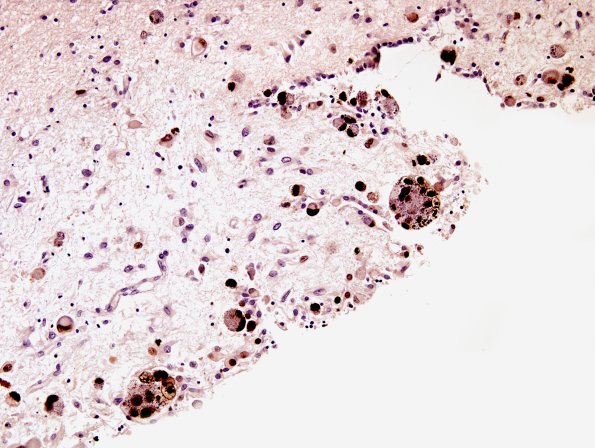

2C2 CMV (Case 2) Ependymitis CMV2

Higher magnification of image #2C1. (CMV IHC)